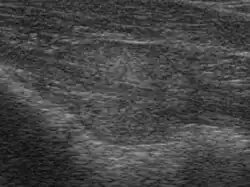

Die Untersuchungsmöglichkeiten der Prostata sind zwar mittlerweile recht vielfältig geworden, aber eine Hauptfragestellung, nämlich ob die Prostata durch einen bösartigen Tumor befallen ist oder nicht, ist nach wie vor zumindest mit den nichtinvasiven Methoden wie dem Ultraschall oder der Computertomographie nur unsicher zu beantworten. Die Prostata des älteren Mannes neigt zur Knotenbildung, und es fällt schwer, mit nichtinvasiven Maßnahmen gutartige von bösartigen Knoten zu unterscheiden. Die Elastographie ist ein neues bildgebendes Verfahren, das Tumorareale aufzeigen und gezielt Gewebeproben entnehmen kann. Auch das sogenannte HistoScanning ist ein neues, ebenfalls ultraschallgestütztes Verfahren zur Detektion von Tumorarealen, um eine gezieltere Prostatabiopsie zu ermöglichen. Bisher ist dieses Verfahren jedoch nur an wenigen Kliniken in Deutschland verfügbar.

Die Prostata kann mit einem Finger rektal ertastet werden. Als bildgebende Verfahren finden bisher Ultraschall, Magnetresonanztomographie (MRT) und Computertomographie (CT) Anwendung. Als spezielles bildgebendes Verfahren zur Diagnose von Prostatakrebs steht die Positronen-Emissions-Tomographie (PET) zur Verfügung, beispielsweise mit 18F-Cholin als radioaktiv markierter Substanz (Tracer), einer Ammoniumverbindung mit dem radioaktiven Fluor-Isotop 18F. Bei Verdacht auf Veränderungen kann eine Biopsie der Vorsteherdrüse mit einer sogenannten Prostatastanze vorgenommen werden. Mit der Elastographie kann wegen der unterschiedlichen Härte Krebsgewebe von Normalgewebe unterschieden werden, so dass gezielt Gewebeproben entnommen werden können. Das HistoScanning misst nicht die Elastizität des Gewebes, sondern durchmustert das Gewebe und greift auf eine große Prostata-Gewebedatenbank zurück, indem mit Hilfe eines Computers ein Datenvergleich mit den Ultraschalldaten und der Datenbank erfolgt. Krebsverdächtige Strukturen werden dabei farblich gekennzeichnet und ermöglichen so eine gezielte Punktion bei der Biopsie.